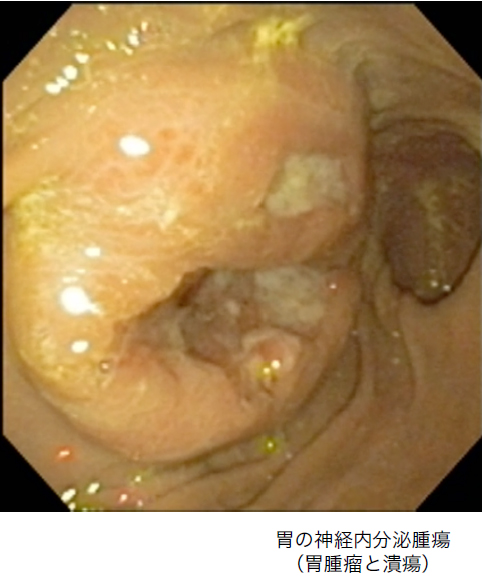

6. 内視鏡検査(上部消化管・下部消化管)

全身麻酔下で消化管粘膜の観察と生検(組織採取)を行い、確定診断を狙います。

• 嘔吐、食欲不振、下痢などが長期化している場合に実施

• 消化器症状とともに体重減少がみられる場合は特に注意

• 慢性腸症、消化管潰瘍、腫瘍などの胃腸疾患の診断に不可欠